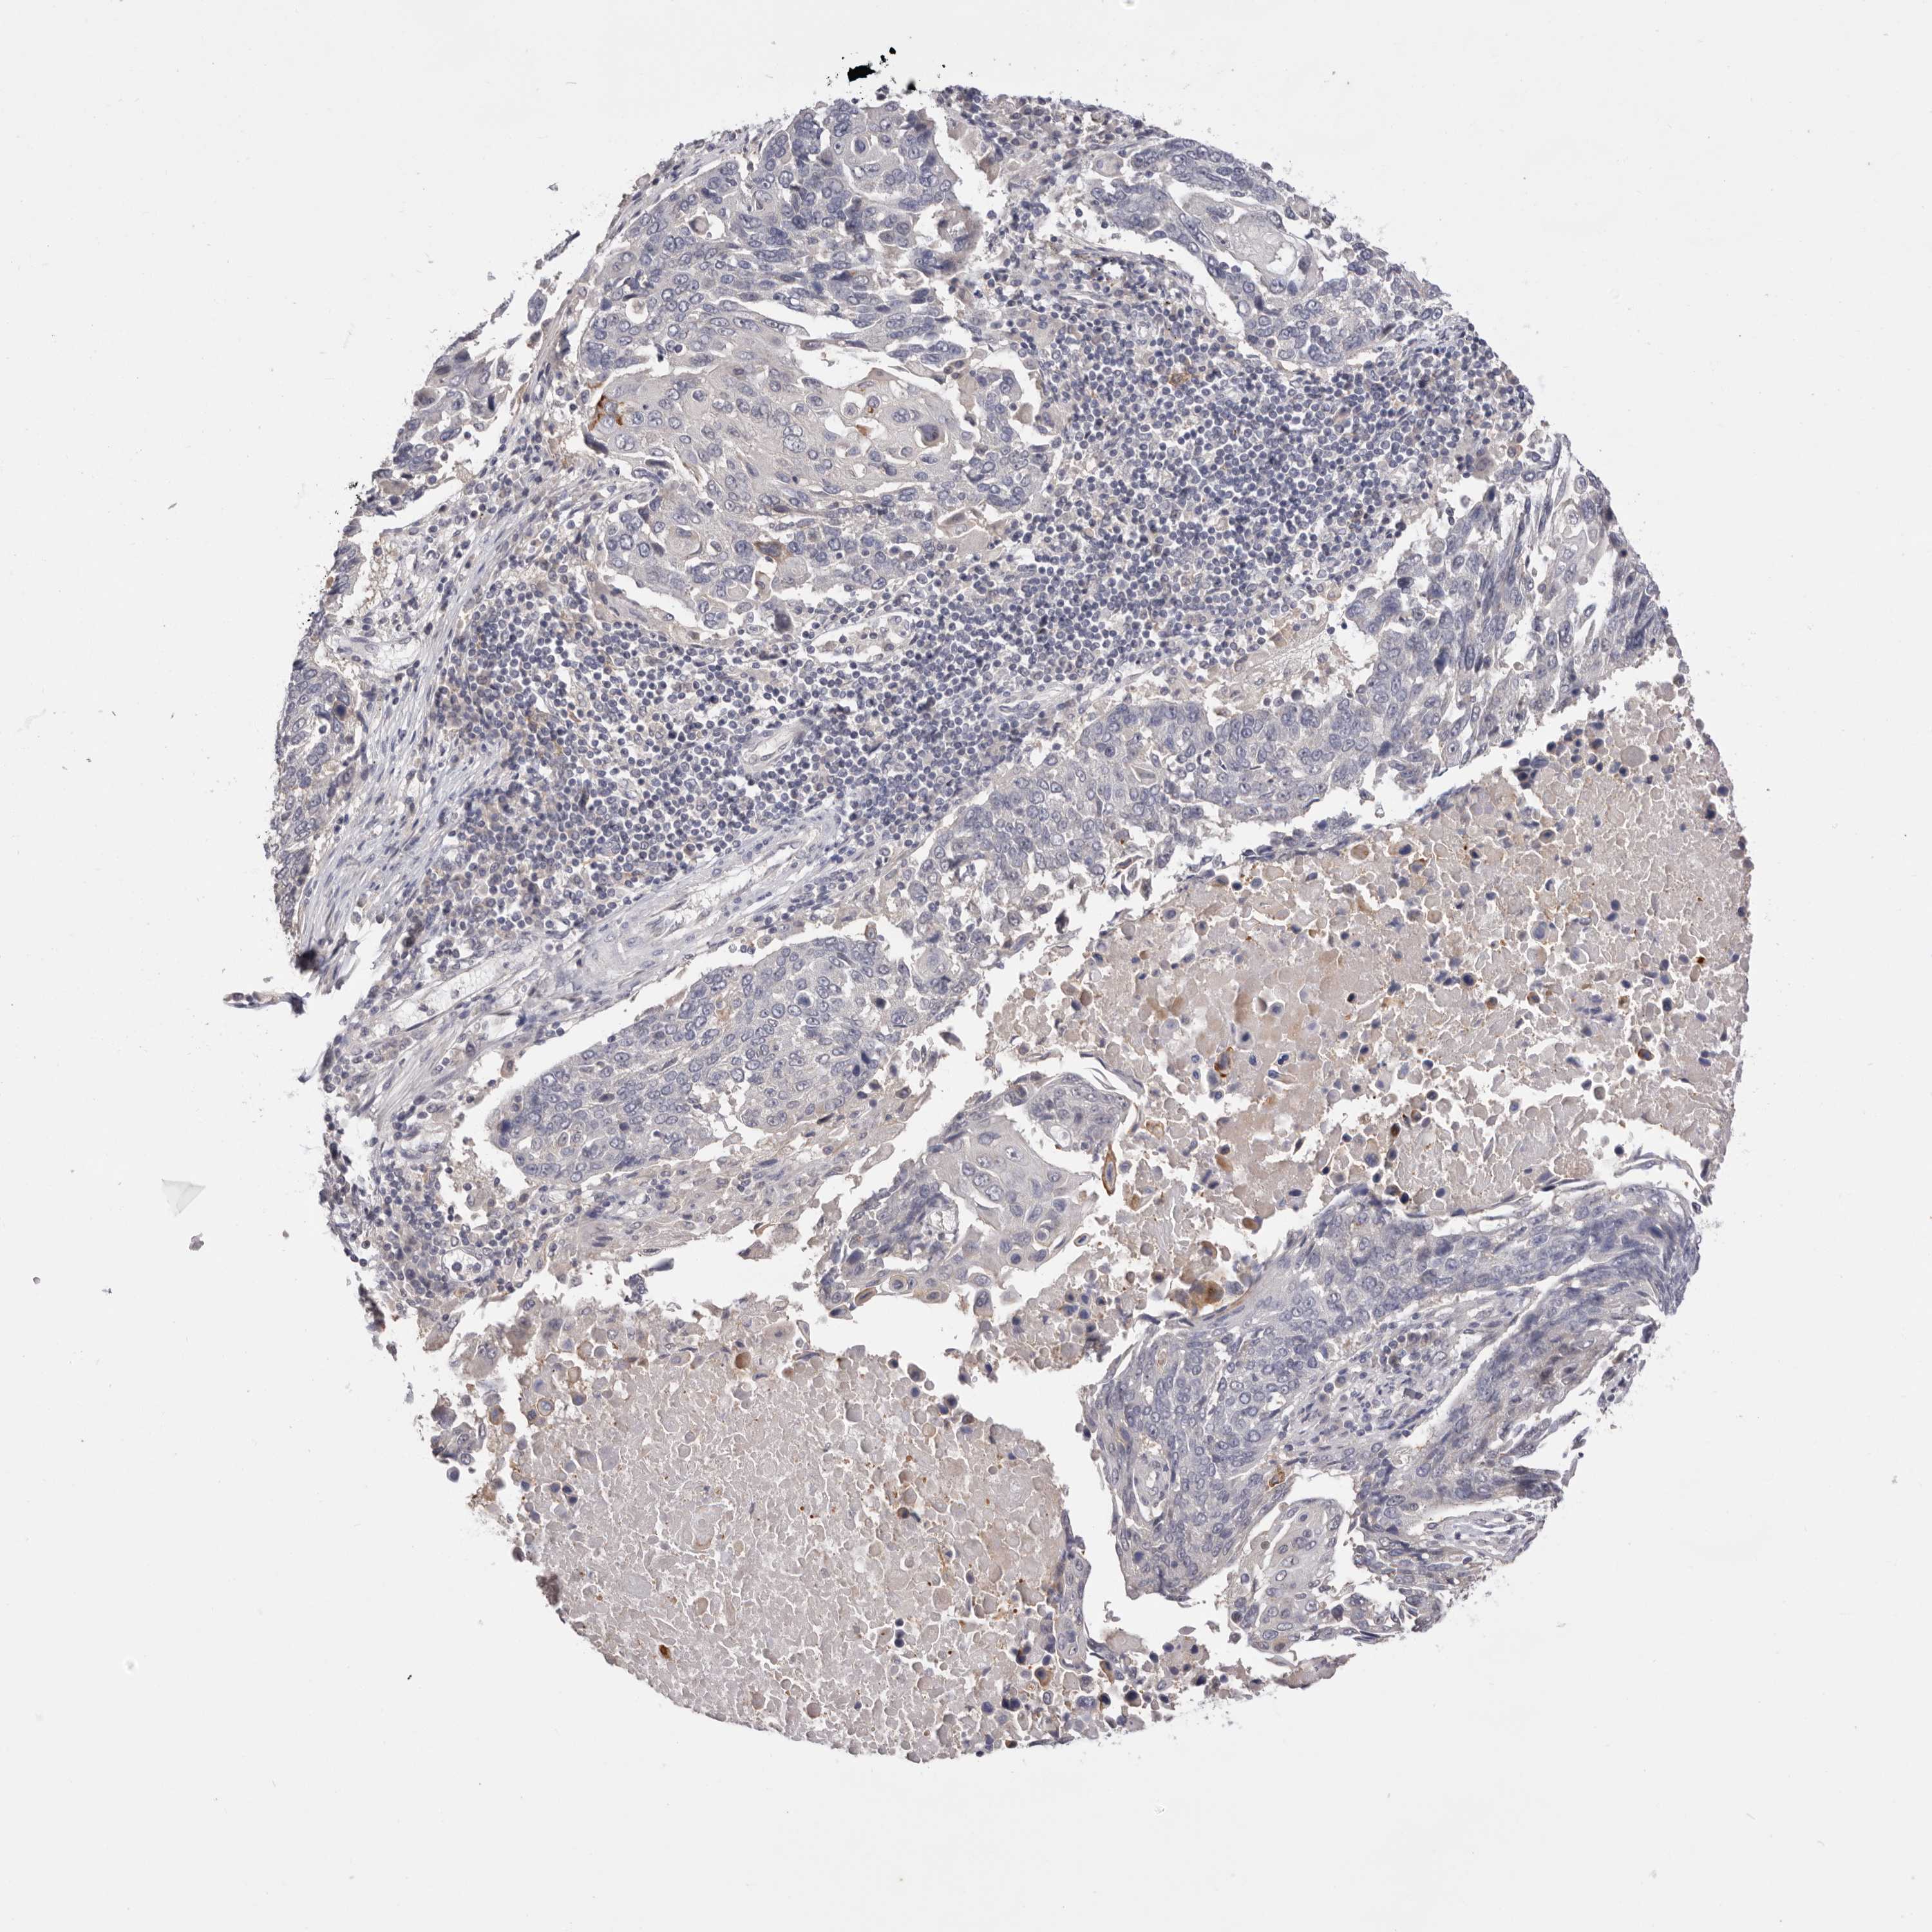

LUNG ADENOCARCINOMA (VALIDATION) - Interactive survival scatter ploti

The Survival Scatter plot shows the clinical status (i.e. dead or alive) for all individuals in the patient cohort, based on the same data that underlies the corresponding Kaplan-Meier plots. Patients that are alive at last time for follow-up are shown in blue and patients who have died during the study are shown in red.

The x-axis shows the expression levels (FPKM) of the investigated gene in the tumor tissue at the time of diagnosis. The y-axis shows the follow-up time after diagnosis (years). Both axes are complimented with kernel density curves demonstrating the data density over the axes. The top density plot shows the expression levels (FPKM) distribution among dead (red) and alive patients (blue). The right density plot shows the data density of the survived years of dead patients with high and low expression levels respectively, stratified using the cutoff indicated by the vertical dashed line through the Survival Scatter plot. This cutoff is automatically defined based on the FPKM cutoff that minimizes the p-score. The cutoff can be changed by dragging the vertical line or by entering a cutoff value in the square labeled "Current cut-off".

Under the Survival Scatter plot the p-score landscape (black curve; left axis) is shown together with dead median separation (red curve; right axis). Dead median separation is the difference in median mRNA expression between patients who have died with high and low expression, respectively. It is calculated as follows: median FPKM expression of dead patients with high expression - median FPKM expression of dead patients with low expression. This is intended to aid the user in visually exploring custom cutoffs and the associated p-scores and dead median separation.

Individual patient data is displayed and can be filtered by clicking on one or more of the category buttons on the top of the page. Categories describing expression level and patient information include: high, low, alive, dead, female, male and tumor stages. The scale of the x-axis can be toggled between linear and log-scale by clicking on the "x log" button. Mouse-over function shows TCGA ID, patient information and mRNA expression (FPKM) for each patient.

& Survival analysisi

Kaplan-Meier plots summarize results from analysis of correlation between mRNA expression level and patient survival. Patients were divided based on level of expression into one of the two groups "low" (under cut off) or "high" (over cut off). X-axis shows time for survival (years) and y-axis shows the probability of survival, where 1.0 corresponds to 100 percent.

DOP1A is not prognostic in Lung Adenocarcinoma (validation)

Best expression cut offi

Based on the FPKM value of each gene, patients were classified into two groups and association between prognosis (survival) and gene expression (FPKM) was examined. The best expression cut-off refers the FPKM value that yields maximal difference with regard to survival between the two groups at the lowest log-rank P-value. Best expression cut-off was selected based on survival analysis .

When clicking on this number, the vertical dashed line indicating cut-off, the interactive survival plot, and the Kaplan-Meier curve will be adjusted to show results based on the best expression cut-off.

: 12.53

P scorei

Log-rank P value for Kaplan-Meier plot showing results from analysis of correlation between mRNA expression level and patient survival.

N/A

TCGA RNA samplesi

RNA-seq data is reported as average FPKM (number Fragments Per Kilobase of exon per Million reads), generated by the The Cancer Genome Atlas (TCGA) .

Normal distribution across the dataset is visualized with box plots, shown as median and 25th and 75th percentiles. Points are displayed as outliers if they are above or below 1.5 times the interquartile range. FPKM values of the individual samples are presented next to the box plot.

Average pTPM 9.5

Number of samples 105